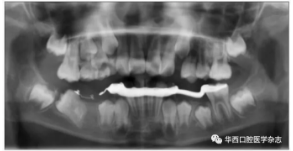

46牙開窗并將舌側扣粘接于近中面。用玻璃離子將鑄造板粘接在下頜,橡皮鏈通過83牙遠中的牽引鉤和46牙上的舌側扣相連,橡皮鏈牽引時對46牙產生一個順時針旋轉的作用力。術中牽引1個月時,見46牙產生順時針旋轉(圖5、6)。治療5個月時,46牙產生明顯的順時針旋轉,基本直立(圖7),由于此時下頜雙側乳尖牙脫落,下頜鑄造板無法固位,于是拆除矯治器,觀察隨診,待后期其余牙齒萌出后行全口固定正畸矯治。

右下頜第一磨牙遠中水平阻生1例

圖  6    治療1個月全景片

圖  7    治療5個月全景片